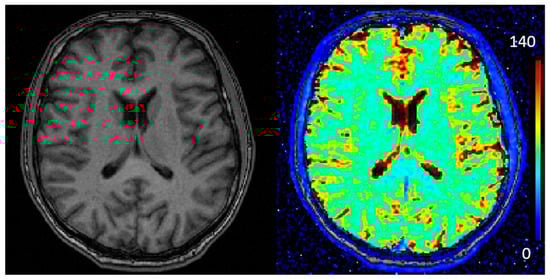

2.5. Relaxometry

2.10. Quantitative T2* Analysis